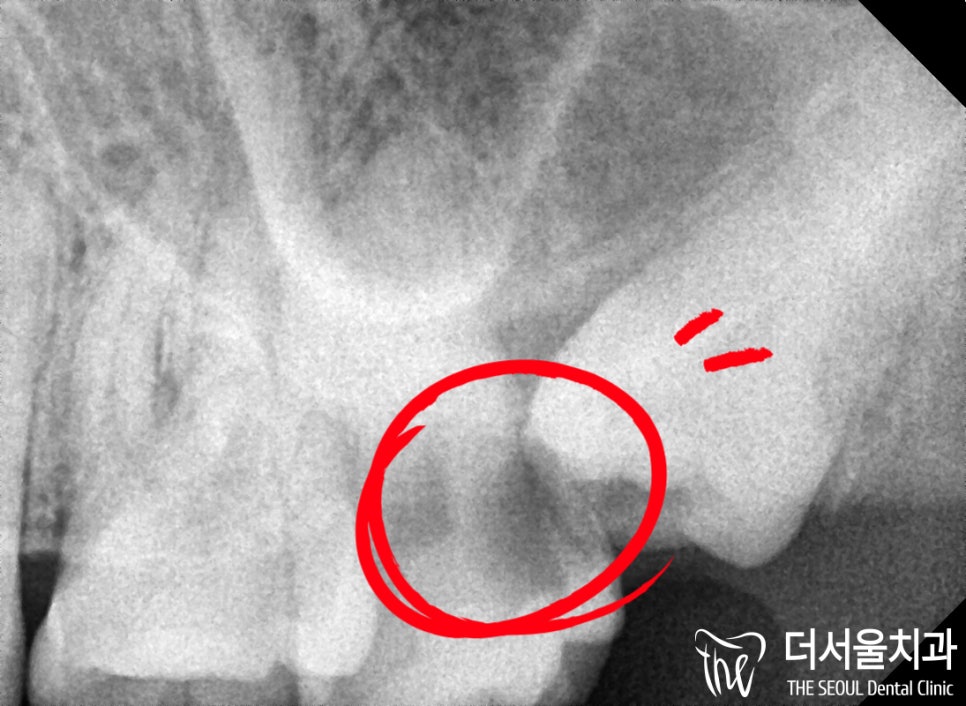

『첫 진료』

환자분께서 오셨을때

사랑니가 나온 것은 알고 있었으나,

크게 별 이상 없을 것이라 생각하여

그대로 방치를 해버렸다고 말씀하셨습니다.

그 결과, 과하게 썩어버렸는데,

그 옆에 있는 어금니까지 덩달아

같이 썩어버리고 말게 된 것이죠.

문제는 옆에 있는 인접면으로부터

충치 균이 침투해버린 탓에

손을 쓰지 못한 채 발치해야 되었습니다.

게다가 썩은 부위를 살펴보면

저렇게 깊게 침투한 것을

확인할 수 있었습니다.

이미 치수까지 깊게 파고들어

신경치료를 해드리기 힘든 상태였습니다.

그리고 뽑아야 되는 사랑니 자체는

공간이 협소하여 뽑기 힘든 케이스였습니다.

아마 다른 곳에서 뽑지 않았던 이유가

그정도로 뽑기 힘들었기에

방치를 해버렸다가 충치로 이어진 것 같습니다.